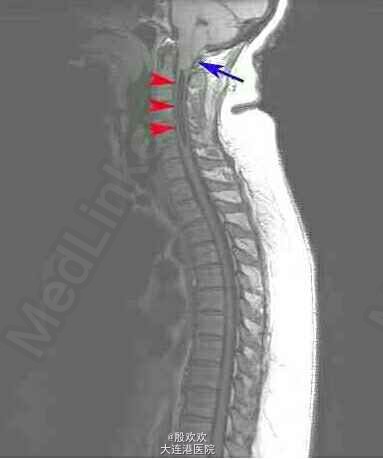

患者,女,51岁,因“右上肢无力萎缩10+年,双上肢麻木5年”入院。患者10+年前感右上肢力弱,逐渐加重,并发现右手肌肉渐萎缩。后双上肢麻木。

查体:生命体征平稳,双上肢皮肤粗糙。专科查体:神清,语利,双侧颈5-胸4水平痛温觉减退。双下肢肌张力稍高,右手骨间肌肉萎缩。双侧腹壁反射消失,双肱二头肌肌腱、肱三头肌肌腱、桡骨膜反射减低,双侧膝反射、踝反射明显增高。 辅助检查:头+颈椎+胸椎MRI:charis畸形并脊髓空洞症。

诊断:脊髓空洞症并小脑扁桃体下疝畸形:charis I型畸形。治疗:给于给于维生素B、ATP、肌苷等营养神经及康复治疗。

脊髓空洞症的病因不明,但是普遍认为,枕大孔区狭窄性病变阻断了脑脊液从脊柱向头部的正常循环,正是因为如此,可以对于charis I型畸形可以行后颅窝减压术,重建脑脊液通路,恢复脑脊液的正常循环状态,虽然少数患者恢复不满意,但大量研究已经证明,其远期疗效肯定。但是临床上,一般先进行内科治疗,如果无效,再和家属沟通性外科手术疗法。